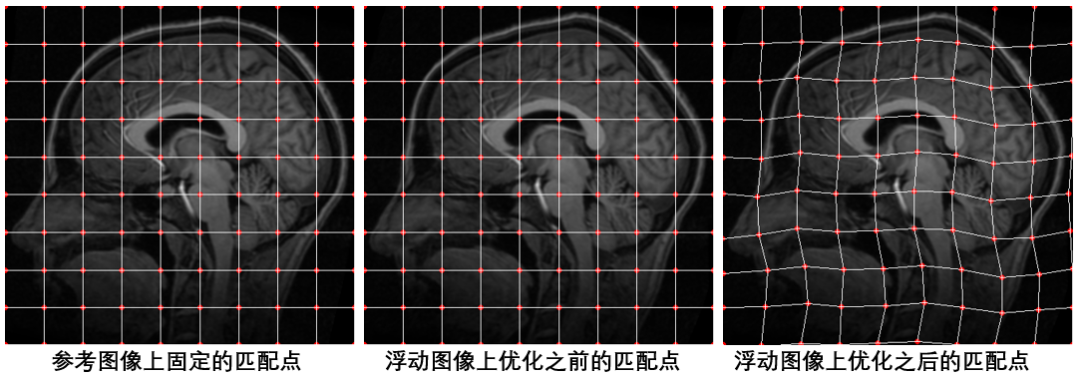

基于此方法,我们不必去找特征点并计算特征点的匹配,在配准开始之前,我们只需要在参考图像与浮动图像上面初始化一系列等间距的点,并假设两图中相同位置的点为匹配点对,然后在此基础上使用梯度下降法一步一步优化浮动图像上初始点的位置,使得浮动图像与参考图像上的点达到真正的匹配。如下图所示:

在这里需要强调的是,我们并不需要优化参考图像上点的位置,我们只需要固定参考图像上点的位置,然后优化浮动图像上点的位置,使其与参考图像上点的位置匹配即可。所以,上面我们说目标函数的输入参数是参考图像与浮动图像的匹配点对,其实需要优化的只有浮动图像上点的位置。假设参考图像与浮动图像上初始化的等间距的点个数都是N个,每个点包含x坐标和y坐标,那么我们需要优化的参数为浮动图像上所有初始化点的x、y坐标组成的2*N个参数。

配准前后初始化点的位置